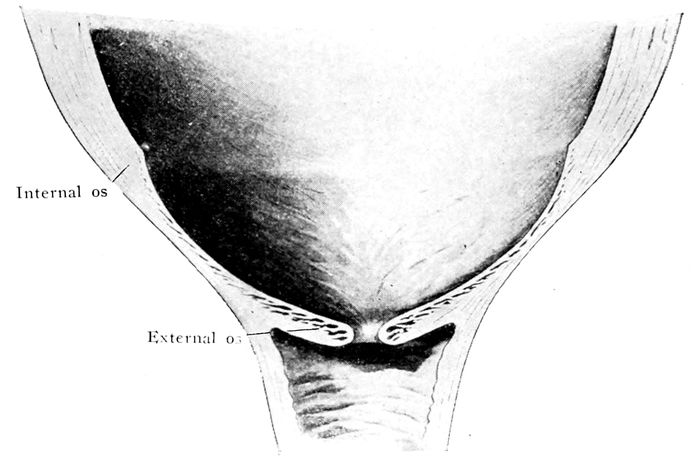

The bag of waters begins to act on the cervix |

111 |

| |

| 36. |

The effect of the pains. The cervix before labor begins |

112 |

| |

| 37. |

The effect of the pains. The cervix begins to be “effaced” |

112 |

| |

| 38. |

The effect of the pains. The cervix is effaced, and the dilatation of the os begins |

113 |

| |

| 39. |

The effect of the pains. The cervix is effaced and the os continues to dilate |

113 |

| |

| 40. |

The cervix is effaced and the os dilated |

115 |